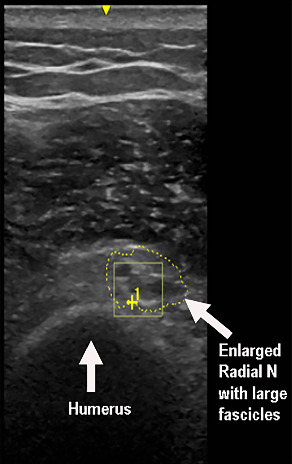

Gorham-Stout病(GSD),也被称为消失骨病或大量骨溶解,是一种罕见的疾病,其特征是骨基质破坏和血管结构增生导致骨吸收。虽然神经系统并发症,如继发于颅脑受累的脑脊液鼻漏和脊髓受累的截瘫已被报道,但周围神经并发症尚不清楚。我们描述了一个病例桡神经麻痹,这是一个医源性并发症的肩关节置换手术与骨丢失的肱骨类似GSD。患者为71岁男性,曾行左侧全肩关节置换术,12年后左侧上臂出现“骨突出”和疼痛。x光片显示肱骨近端未见。左上肢CT扫描显示肱骨部分松动,远端干周围明显骨溶解。患者接受了反向全肩关节置换术的翻修,并置换了肱骨头和肱骨干。患者术后出现左肩、左臂麻木、疼痛、无力及手腕下垂。体格检查显示腕、指背屈肌明显无力,肱桡肌消瘦无力,桡浅神经分布针刺感丧失。针刺肌电图显示指掌伸肌、肱桡肌和桡侧腕长伸肌的去神经支配改变。超声检查显示左侧桡神经螺旋沟肿大。EDX和US显示左桡神经在螺旋沟处麻痹。三角肌和肱三头肌肌电图异常轻微,提示臂丛后束受累。本病例说明了肩关节置换术后可能发生医源性桡神经麻痹,肱骨骨明显丢失,类似GSD。

Gorham-Stout disease (GSD), also known as vanishing bone disease or massive osteolysis, is a rare entity characterized by destruction of the osseous matrix and proliferation of vascular structures resulting in bone resorption. While neurological complications such as cerebrospinal rhinorrhea secondary to cranial involvement and paraplegia from spinal involvement have been reported, peripheral nerve complications are not known. We describe a case of radial nerve palsy that was an iatrogenic complication of shoulder replacement surgery with bone loss of the humerus resembling GSD. A 71-year-old male with a history of left total shoulder arthroplasty followed by a revision reverse total shoulder arthroplasty noted a "bone protruding" and pain in the left upper arm 12 years later. X-rays showed that the proximal portion of the humerus was not detectable. CT scan of the left upper extremity revealed loosening of the humeral component with prominent osteolysis most pronounced around the distal stem. The patient underwent a revision of the reverse total shoulder arthroplasty with replacement of the humeral head and shaft. He experienced numbness, pain, and weakness of the left shoulder and arm with wrist drop postoperatively. Physical exam revealed marked weakness of the dorsiflexors of the wrist and digits, wasting and weakness of the brachioradialis muscle, and loss of pinprick sensation of the superficial radial nerve distribution. Needle EMG showed denervation changes in the extensor digitorum communis, brachioradialis, and extensor carpi radialis longus muscles. An ultrasound (US) study showed enlargement of the left radial nerve at the spiral groove. The EDX and US findings suggested a left radial nerve palsy at the spiral groove. There were minimal EMG abnormalities in the deltoid and triceps muscles suggesting additional involvement of the posterior cord of the brachial plexus. This case illustrates the potential for iatrogenic radial nerve palsy following shoulder replacement surgery with significant bone loss of the humerus resembling GSD.